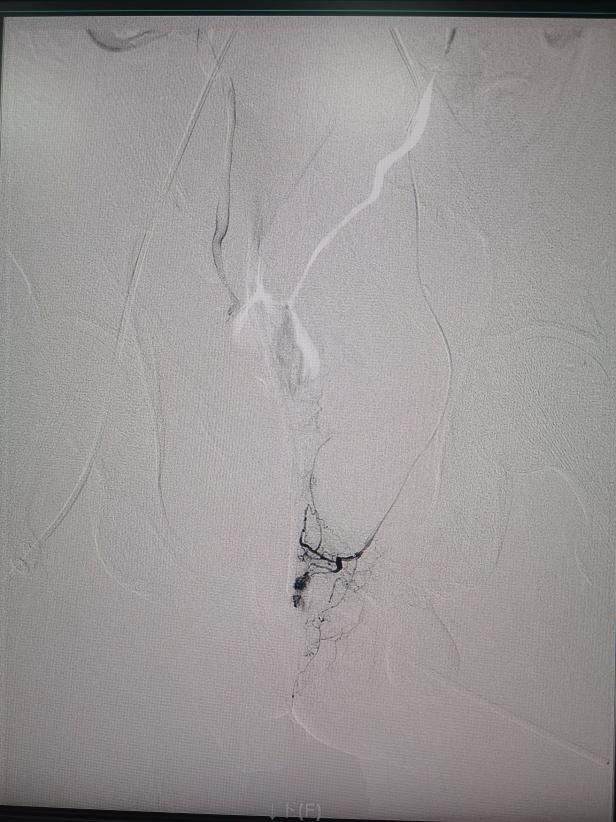

手术中,介入治疗医学中心主任罗阳带领医师林杰、李思刚,借助DSA影像实时引导,精准锁定左侧髂内动脉远端分支的出血点。

面对骨盆骨折后复杂的血管情况,专家们精细操作,如 “穿针引线” 般直达出血分支,用明胶海绵颗粒成功堵住 “漏水口”!术后造影显示,靶血管血流截断,外溢征象完全消失。出血完全停止,手术非常成功!